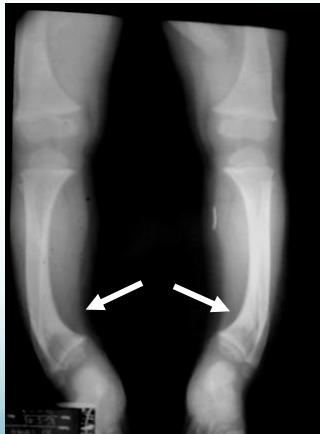

Blount’s Disease

Indications: X-ray when severe or possibly pathologic

Recommended Views:

- Standing AP film: Long film (hips to ankles) with patellae directed forwards

Conditions to Look For:

Tibia vara (Blount’s disease)